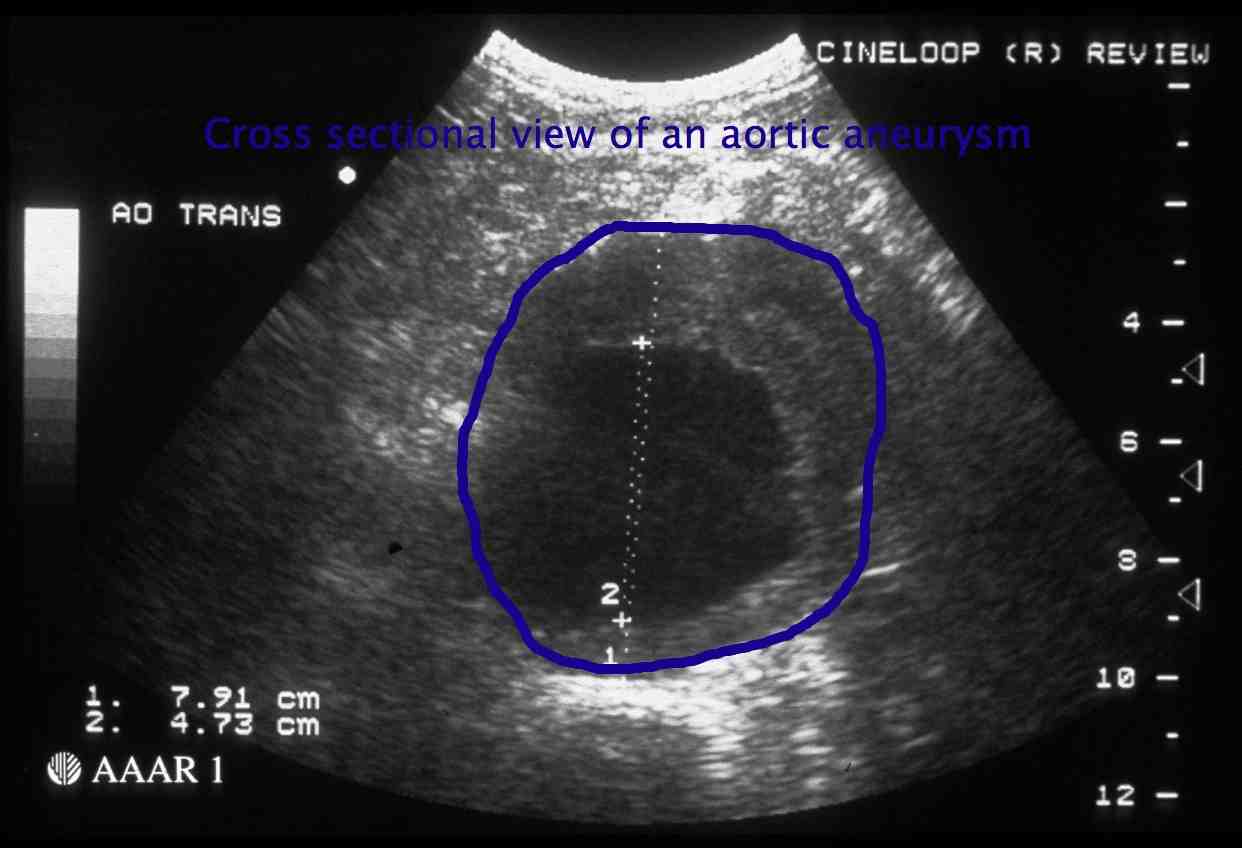

At present in New Zealand there is no screening programme. If a screening programme were to be developed it might work as described below. You would be invited to attend for a free ultrasound scan if you were a man between the ages of 65 and 74 yrs old. An ultrasound scan is a scan commonly used to examine the baby during pregnancy. It is safe and painless and usually will only take a few minutes to determine whether an AAA is present. Examples of ultrasound scans are shown in the black, white and blue images. Patients with a normal scan will not usually need any further follow up.